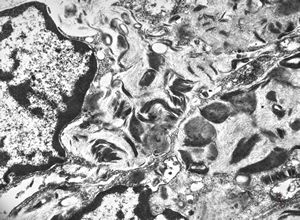

F, 1m. | sepsis - mycotic dermal lesions

M, 57y. | dermal mycotic lesion

M, 57y. | dermal mycotic lesion … toluidine-blue stained semithin section